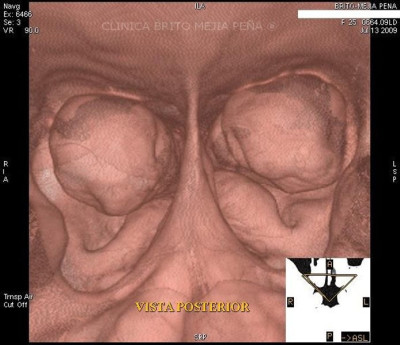

Endoscopía virtual hipertrofia cornetes